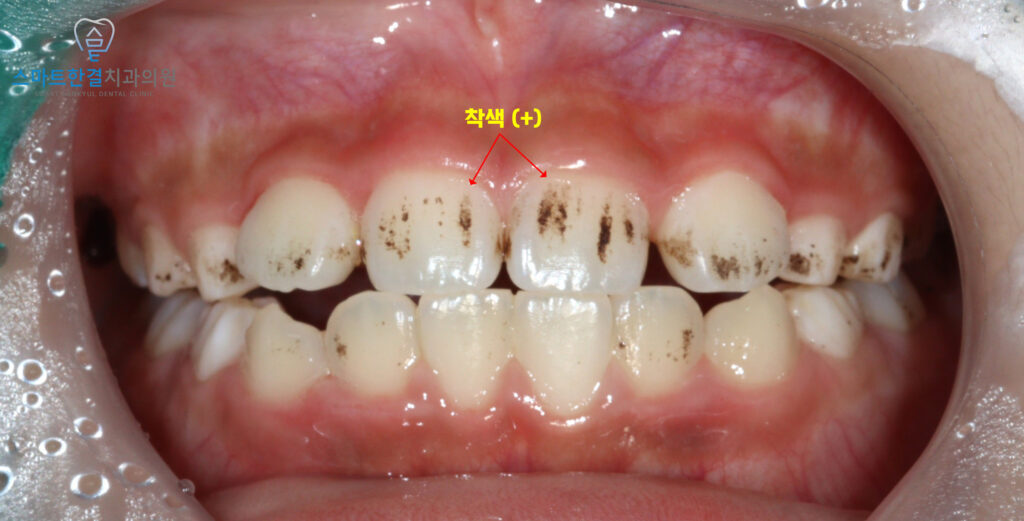

위 환자분께서는 소아 환자분으로

치아가 전체적으로 까맣게 보여

부모님께서 충치가 생긴줄 알고

급하게 내원해 주셨어요.

확인 해보니,

다행히 충치는 아니었고

치아 표면에 착색이 생긴

상황으로 확인되었어요.

소아에게 나타나는 이런 착색은

음식물 색소나 구강 내 세균 배합에 의해

생기는 경우가 많으며,

외관상 진하게 보여

충치로 오해되기 쉬워요.